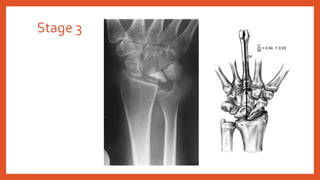

• Stage 3: Lunate collapse

• 3A: Normal scaphoid alignment

• 3B: Fixed scaphoid rotation (Ring sign)

Stage 3